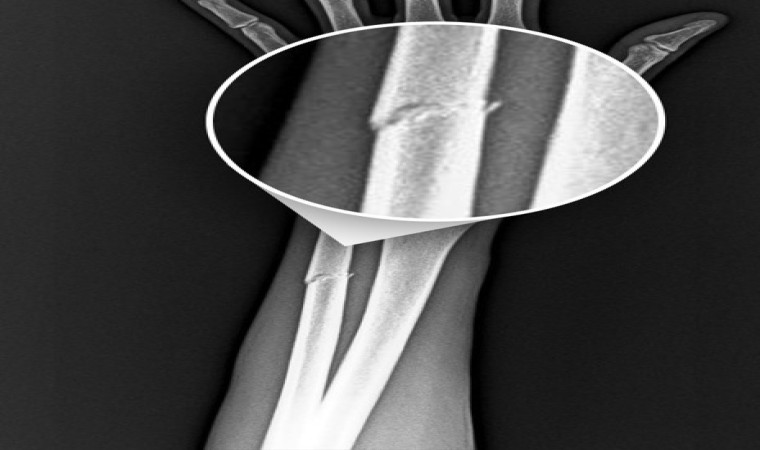

RAMS Başakşehir ile oynanan karşılaşmada mücadele sırasında sakatlanarak oyundan alınan Onuachu’nun sağlık durumu ile ilgili kulübü Trabzonspor bir açıklama yaptı. Yapılan açıklamada, "Futbol A takımımızın Başakşehir ile oynadığı karşılaşma esnasında sakatlanarak oyundan çıkan futbolcumuz Paul Onuachu’nun yapılan muayenesinde sol kasık bölgesinde kas (adduktor kas grubu) yaralanması ve sol ön kolda darbeye bağlı ayrışmamış kemik (ulna) kırığı tespit edilmiştir. Oyuncumuzun tedavisine sağlık ekibimizce başlanmıştır. Oyuncunun sahalardan ne kadar süre uzak kalacağı yapılacak tedavinin ardından belli olacak" ifadelerine yer verildi.